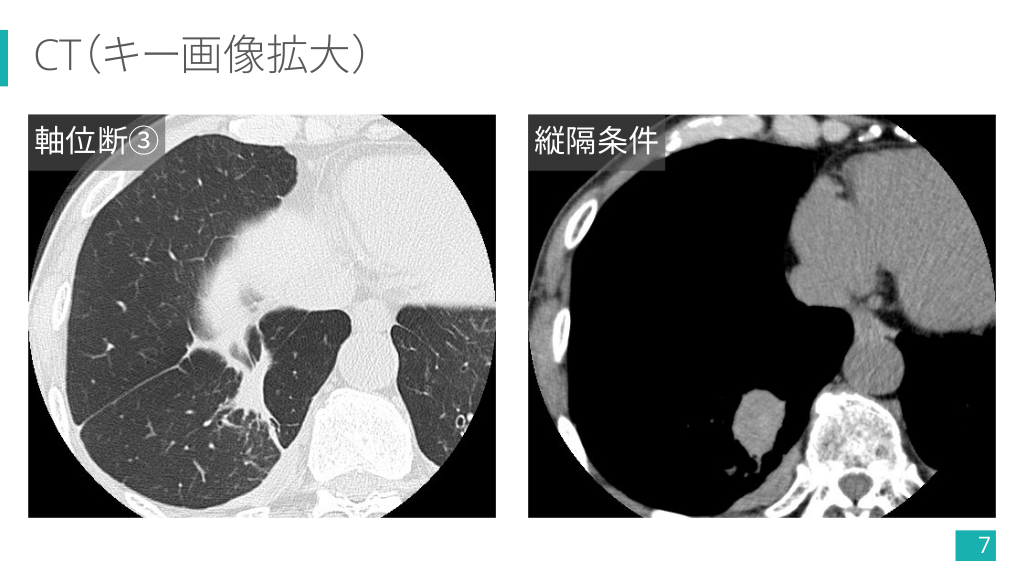

CT(キー画像拡大) 軸位断③ 縦隔条件 7

CT(キー画像) 多発胸膜プラーク(一部石灰化+) 右肺下葉の卵円形腫瘤 14

CT(キー画像) 腫瘤へと曲線的に収束する気管支血管束 (comet tail sign) 15

1-5) 円形無気肺の画像診断 Ø 肥厚した胸膜から連続し,胸膜と 鋭角をなす円形/卵円形腫瘤. Ø 腫瘤に向かい,気管支血管束が曲 線的に収束する像 (comet tail sign) が特徴的. Ø 造影効果は様々. 5) より引用 28

今回の症例で診断の流れを復習!! ① 胸膜プラークが多発してるし, アスベスト曝露ありそうだな〜. ② 右下肺野に腫瘤影あるな〜. ③ CTでも胸膜プラーク多発してる. ④ 右肺下葉の腫瘤は胸膜から連 続して comet tail sign もありそう. ⑤ FDG の集積も縦隔より弱い!! 円形無気肺でよさそう 34